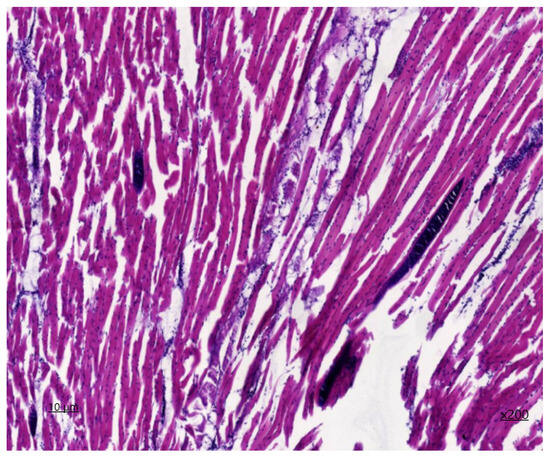

In the preparation of the oesophagus stained with hematoxylin and eosin (Figure 3) and Van-Gizon (Figure 4), a slice of transverse striated skeletal muscle tissue is identified. In the majority of cases, longitudinal and partially transverse sections of muscle fibers are identified.

The perimysium is thickened as a result of the proliferation of connective tissue components, which is indicative of fibrosclerosis. Single nerve trunks are identified, and the density of vessels is augmented in areas of neoangiogenesis. The density of endomysial gaps is increased, as is the number of fibroblast nuclei. Additionally, multiple areas of fibrous fibre sprouting are detected. The sarcoplasm is slightly thickened, with muscle fibre nuclei located parallel to the periphery of the longitudinal line of the muscle fibre. In unaffected muscle fibres, transverse striation is preserved, and myoglobin saturation is sufficient. The diameter of the muscle fibres reaches up to 45 μm. In the histological section, areas of lesions with sarcocysts are observed, with an average of four cysts present. The affected muscle fibres display a lack of transverse striation, and the sarcoplasm forms a connective tissue capsule of varying shapes, including lemon-shaped, oval, and rounded. Second-generation meronts, which are filled with endozoites measuring 103 × 52 µm in size, are also present. On the periphery of the cyst capsule, a non-specific inflammatory response is observed, characterised by the presence of a histiocytic component with an admixture of lymphocytes. The degree of inflammation of the muscle tissue at a distance from the lesion area is visualised in the form of chronic myositis of focal character. In histochemical Van-Gizon staining, fibrous fibres exhibit a bright crimson hue, with increased density and occurrence due to concentric structures on the periphery of neurovascular bundles and due to the thickening of perimysium fibres deeply embedded in endomysial spaces.

Figure 3. Sarcocystis in the oesophagus, second-generation meronth staining with haematoxylin and eosin ×200.

Figure 4. Sarcocystis in the oesophagus, second-generation merontium Van-Gizon staining ×200.